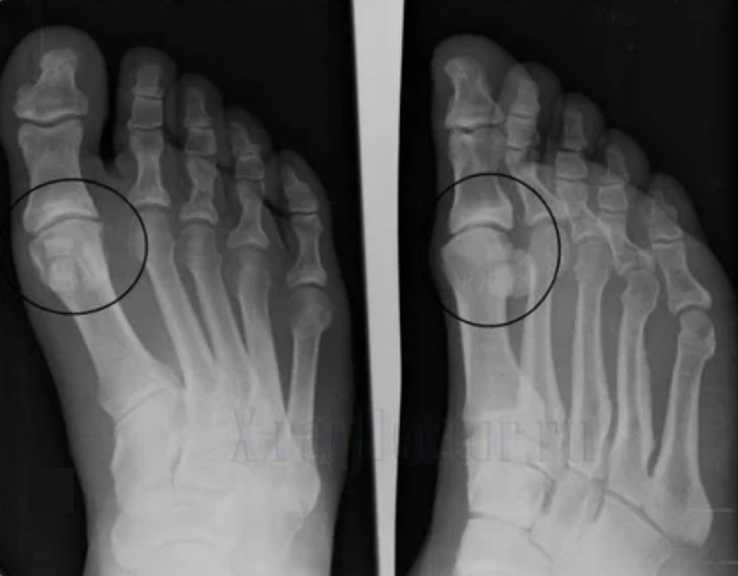

Pour poser un diagnostic, les rhumatologues examinent les symptômes du patient et prescrivent un examen X-Ray. La plupart du temps, la radiographie est utilisée dans 2 projections. Le médecin examine la présence de troubles dystrophiques dans le cartilage hyalin et les articulations osseuses. Lorsque l'espace articulaire est réduit, les os sont déformés ou aplatis, il existe des formations kystiques à la surface du cartilage, les ostéophytes sont des signes évidents d'arthrose. Pendant l'inspection, l'arthrose montre l'instabilité de l'articulation: l'axe des membres et la subluxation est perturbé.

Souvent, une image de rayons x n'est pas en mesure de fournir des informations complètes sur l'état de l'articulation. La tomographie par ordinateur est prescrite pour une étude plus approfondie et il est efficace d'examiner les os. L'IRM est utilisée plus souvent pour examiner les tissus mous.